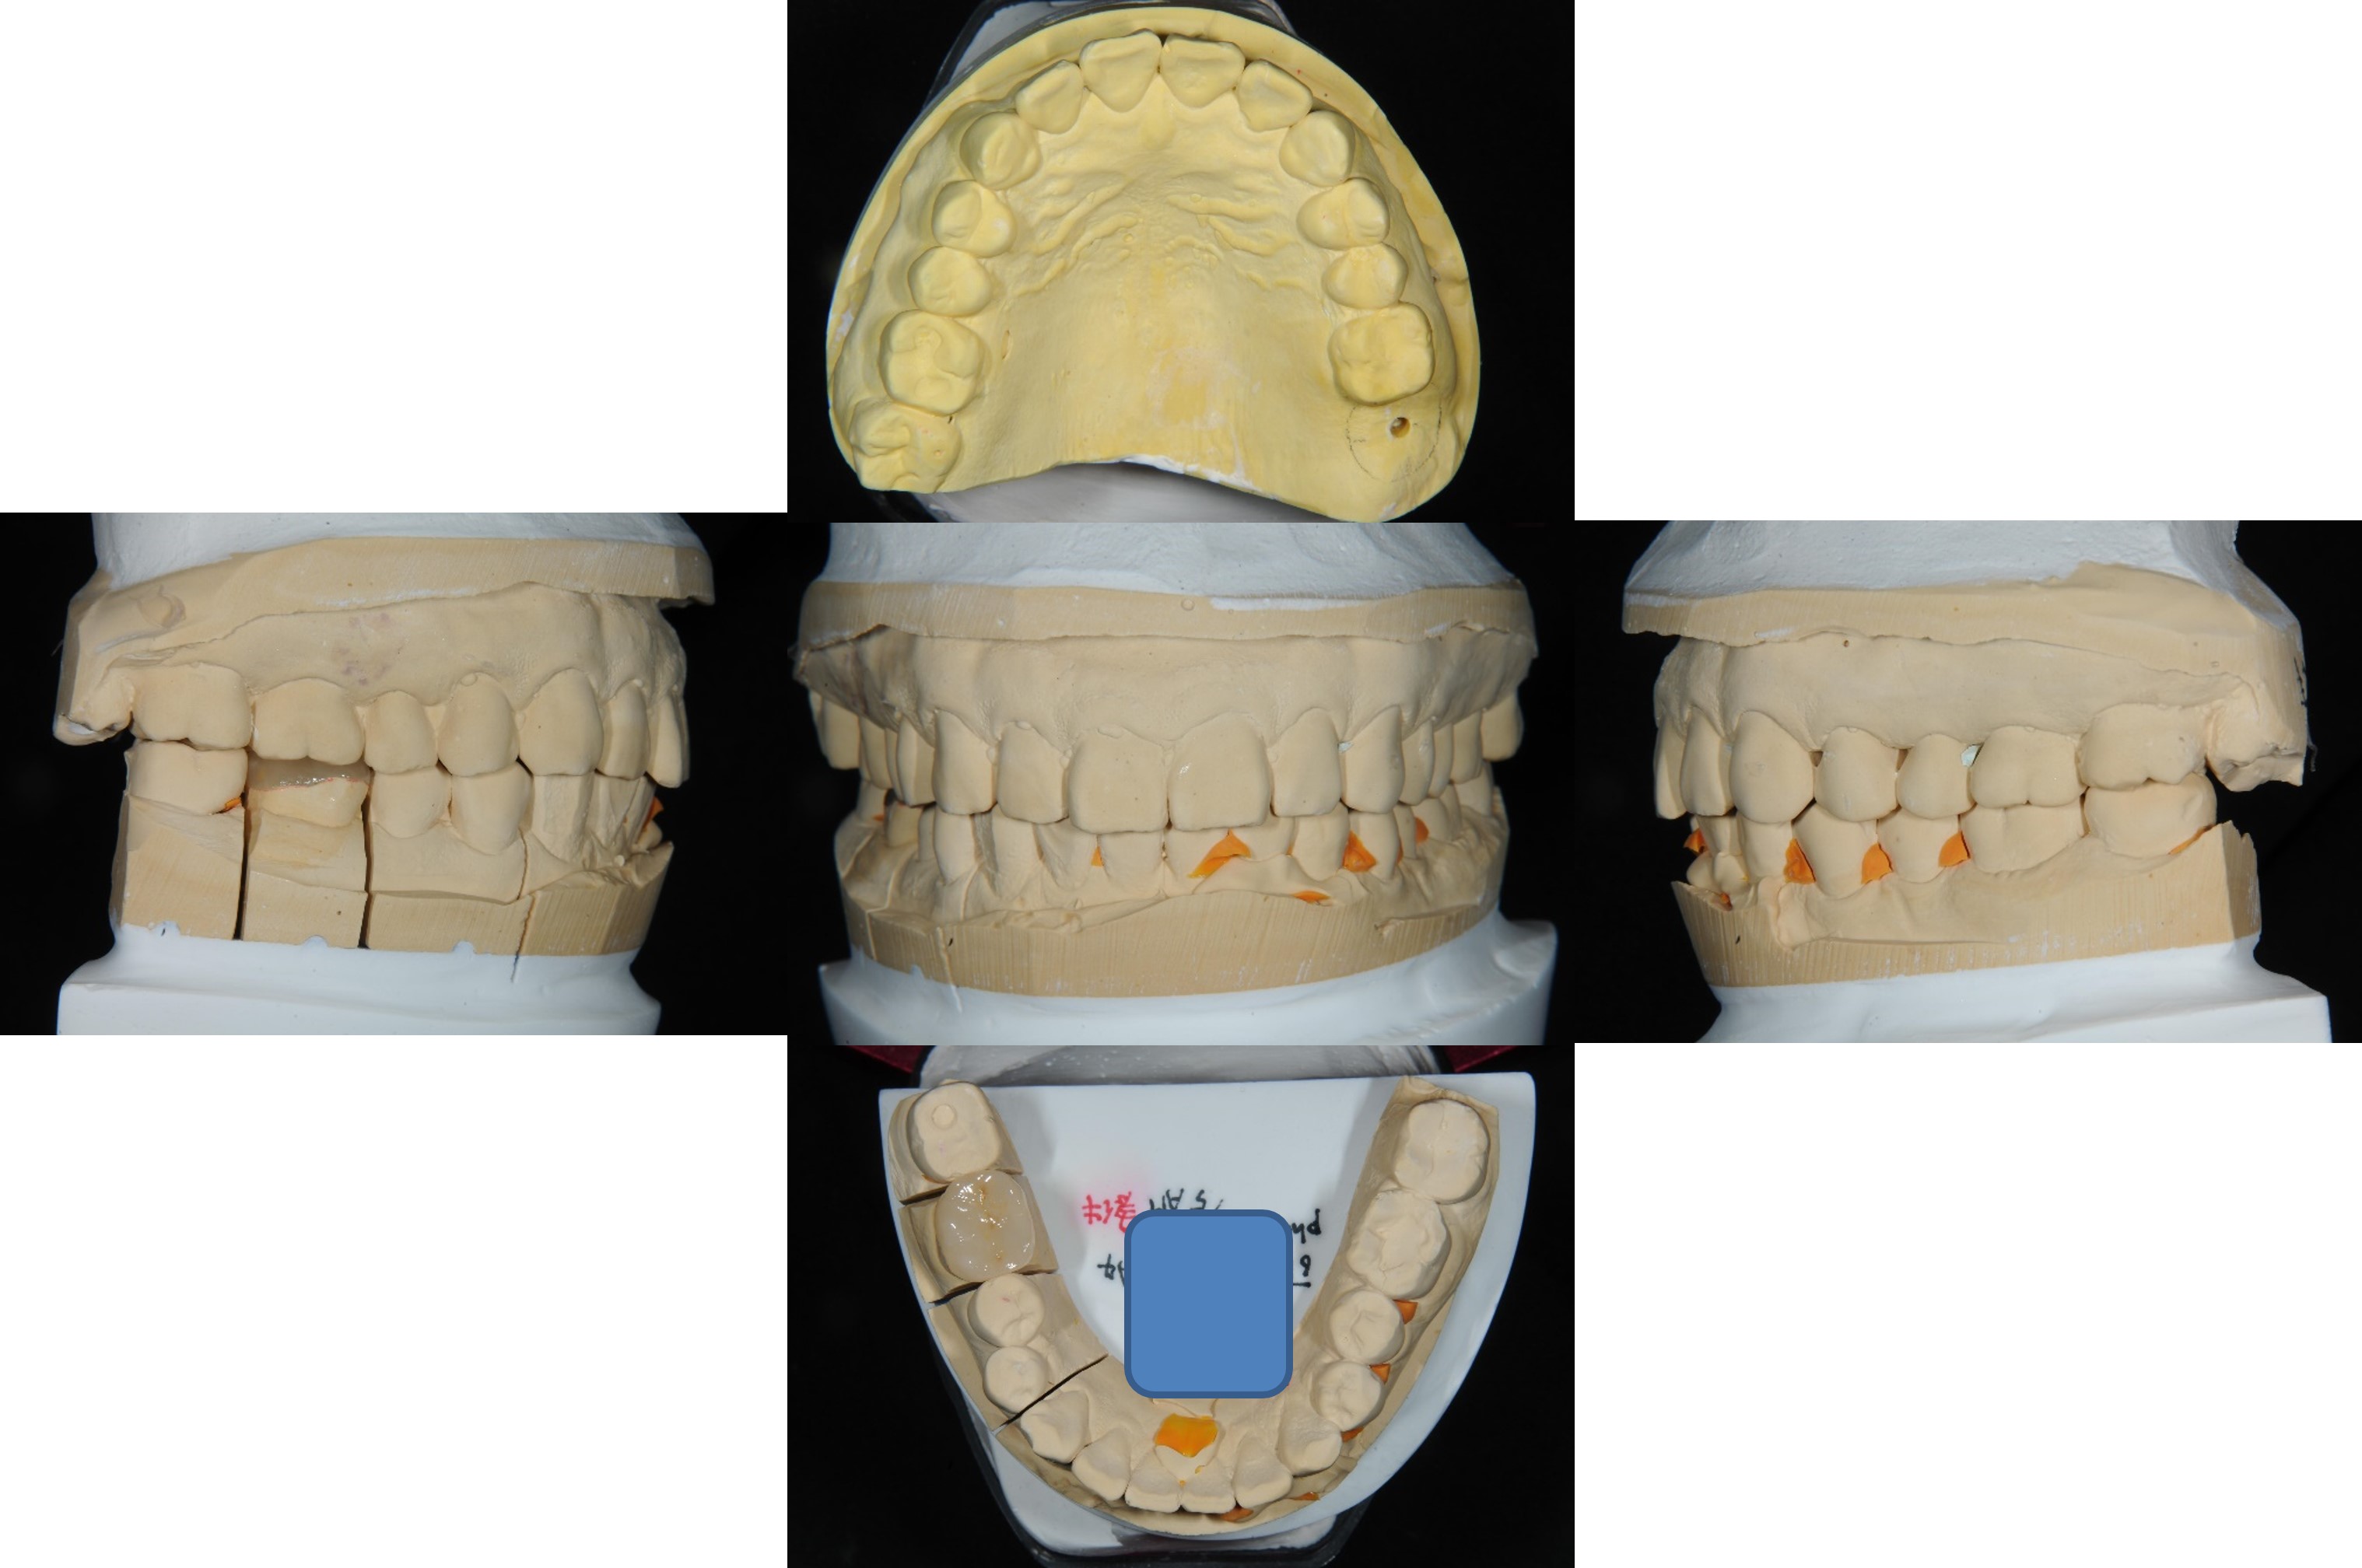

上面弓,咬合器

陶瓷冠塊體製作

陶瓷冠塊體